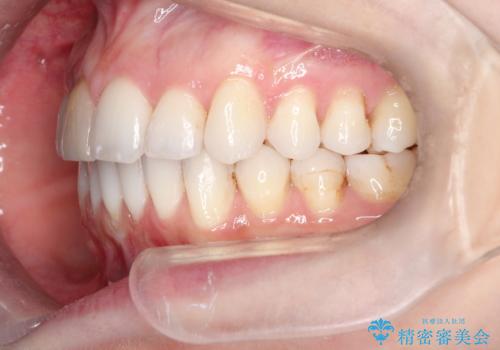

インビザラインによる非抜歯での八重歯の矯正

- 左上の八重歯と、上の歯のがたつきを主訴に来院されました。

上の奥歯を後方に移動させてスペースを作るのと、歯と歯の間をわずかに削り歯を並べる計画としました。

非常に強力的な患者様であったので、上下の正中も合わせ、ガタガタも改善することができました。